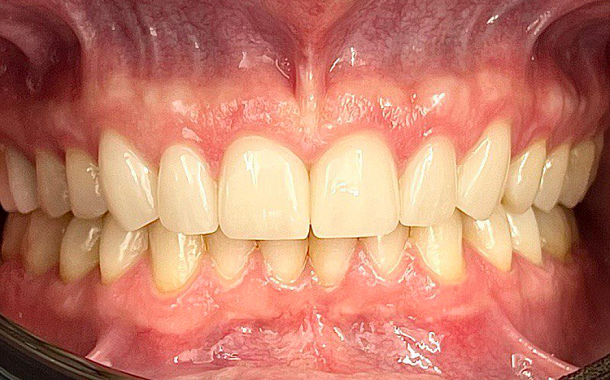

Высочайшая точность для идеальной посадки

Aoralscan 3 обеспечивает сканирование с точностью до 6,9 мкм, что позволяет создавать максимально точные цифровые слепки. Это критически важно для изготовления коронок, мостов, виниров и других ортопедических конструкций, гарантируя их идеальную посадку и долговечность.Скорость и комфорт для пациентов

- Максимально точные и эстетичные ортопедические конструкции